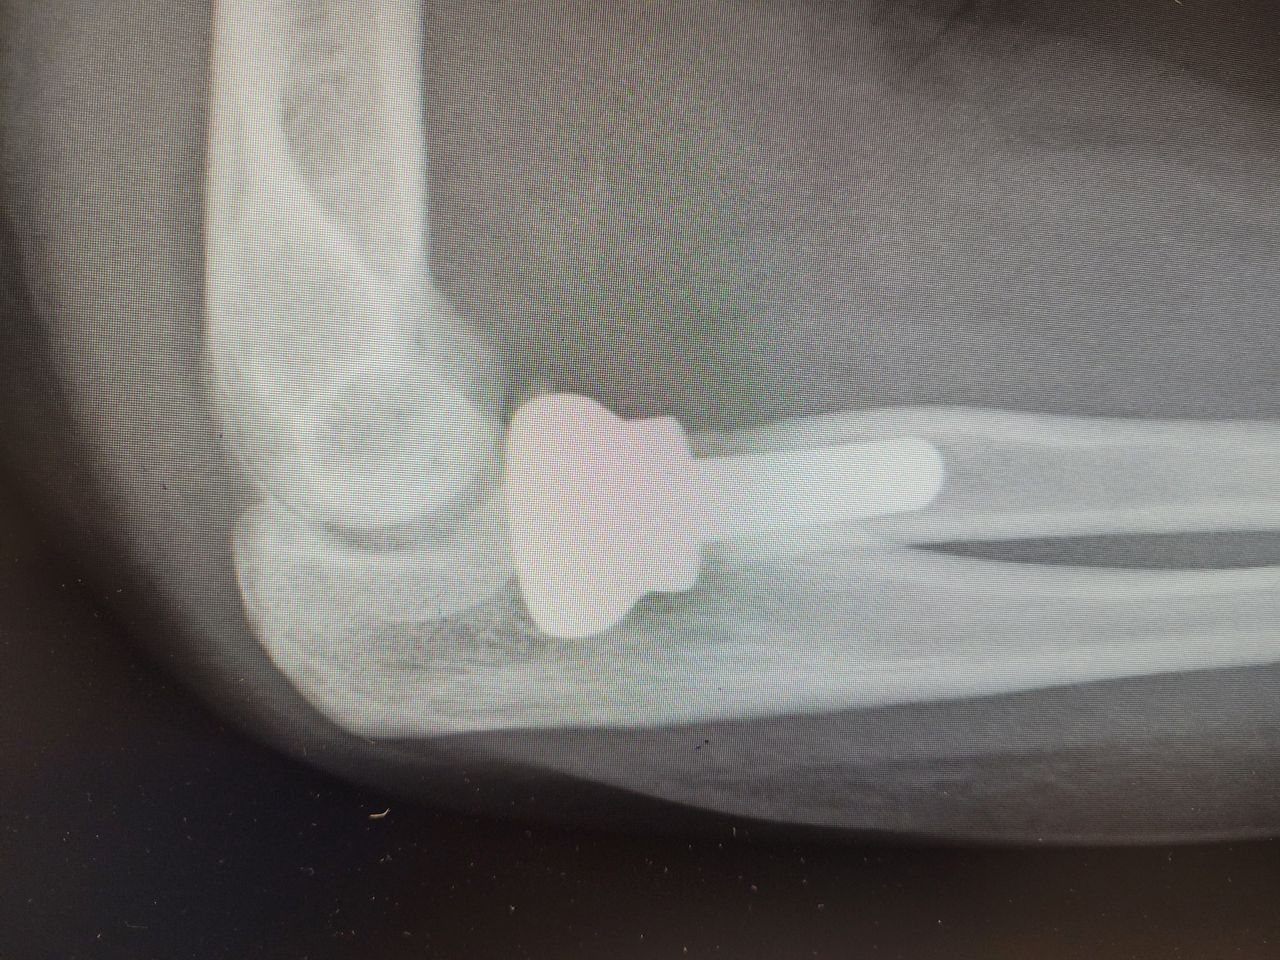

Endoprotezy stawów ręki ( kciuk, paliczki, nadgarstek ).

Zdjęcia i filmy